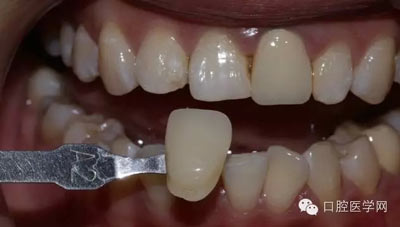

1、術(shù)前比色照

將比色照飽和度調(diào)到最低有助于牙齒明度的選擇